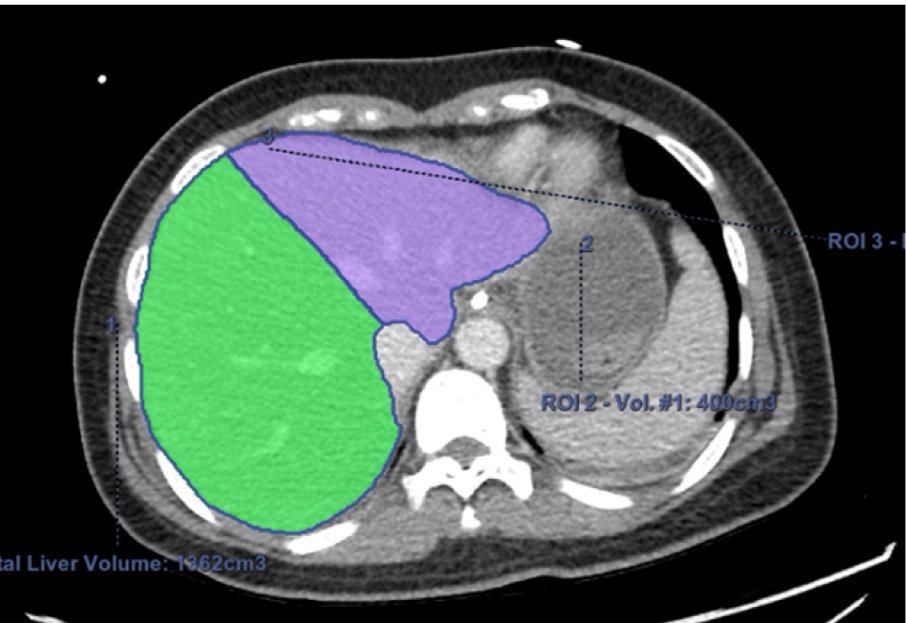

بحمد الله تم نشر هذه الورقة العلمية عن #زراعة_الكبد بعد تقسيمها الى فصين من متوفية دماغياً لكي يستفيد منها مريضين على قائمةالإنتظار

👈 المبدأ الثاني (وهو ما اتبعناه نحن) هو تقسيم الكبد من متوفي دماغيا الي نصفين كاملة تقريبا وكان الجانب الأيسر(الوريد الكبدي الأيسر+الوريد الكبدي الأوسط) لمريض بالغ صغير الحجم والجانب الايمن لمريض بالغ متوسط الحجم.